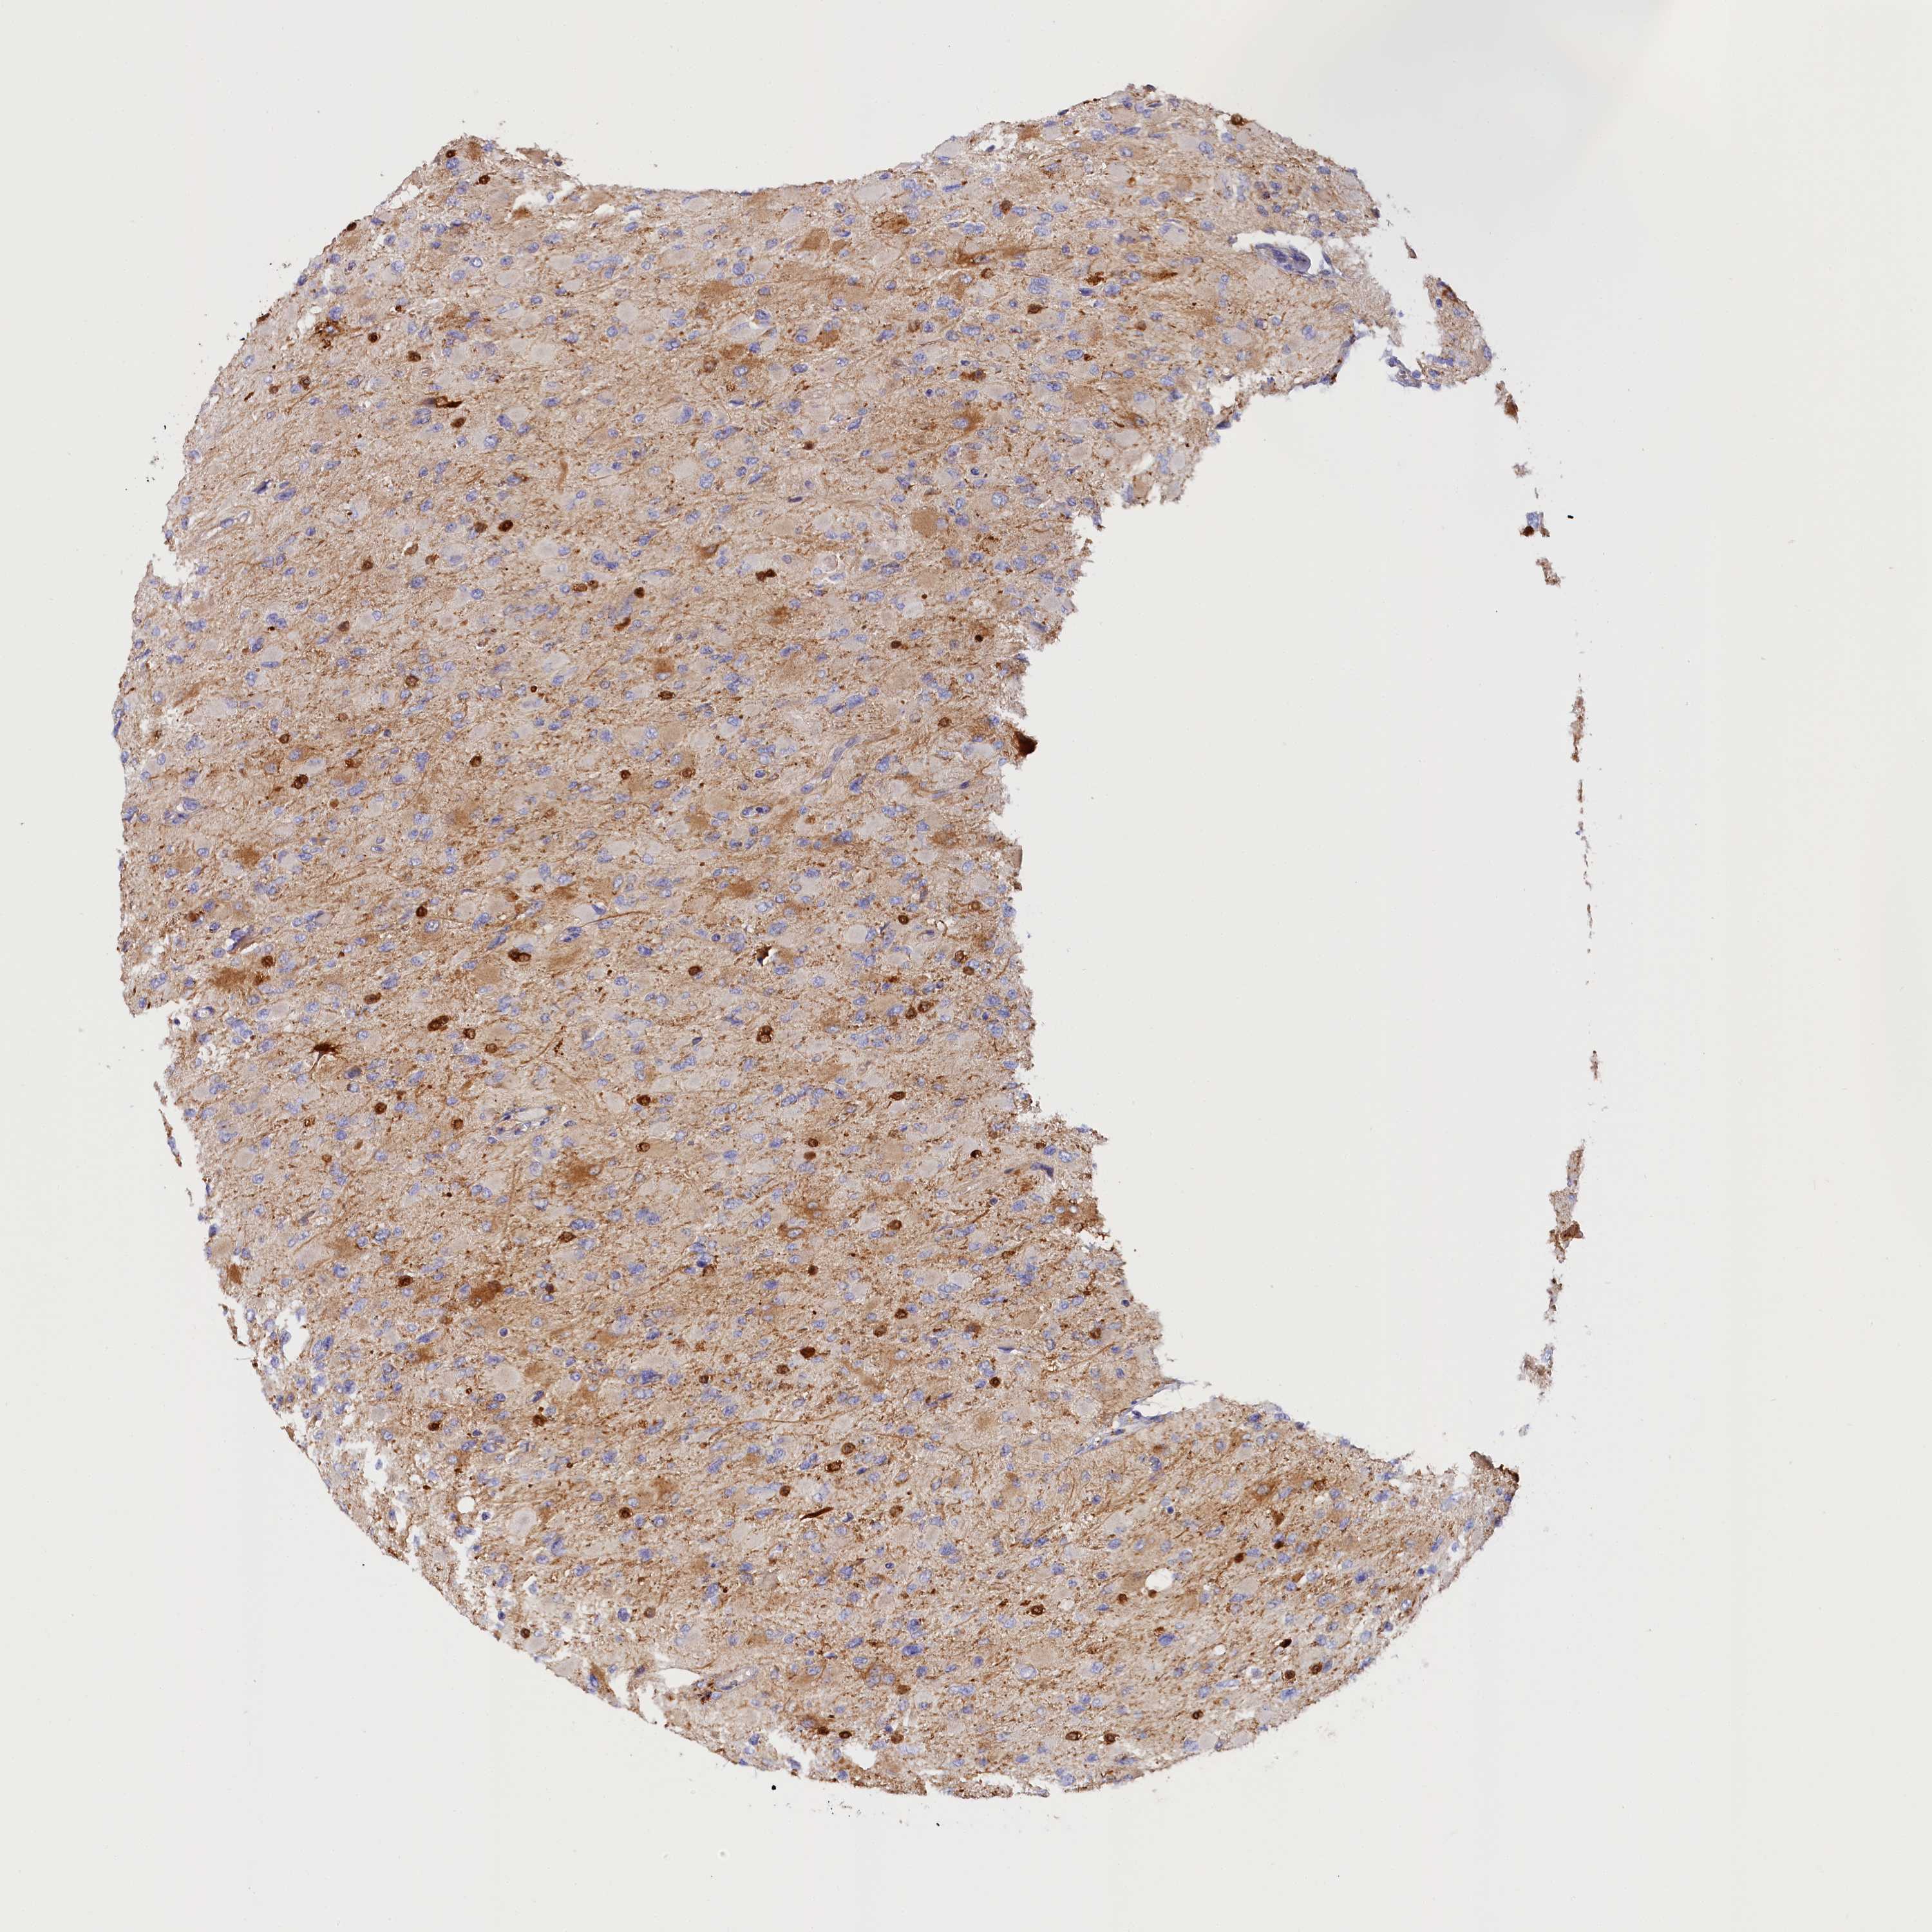

GLIOMA - Protein expressioni

A mouse-over function shows sample information and annotation data. Click on an image to view it in a full screen mode. Samples can be filtered based on level of antibody staining by selecting one or several of the following categories: high, medium, low and not detected. The assay and annotation is described here.

Note that samples used for immunohistochemistry by the Human Protein Atlas do not correspond to samples in the TCGA dataset.

Antibody stainingi

Antibody staining in the annotated cell types in the current human tissue is reported as not detected, low, medium, or high, based on conventional immunohistochemistry profiling in selected tissues. This score is based on the combination of the staining intensity and fraction of stained cells.

Each image is clickable and will lead to virtual microscopy that enables deeper exploration of all samples and also displays staining intensity scores, fraction scores and subcellular localization as well as patient and tissue information for each sample.

Antibody HPA041165

Antibody HPA041839

Staining

High

Medium

Low

Not detected

Intensity

Strong

Moderate

Weak

Negative

Quantity

>75%

75%-25%

<25%

None

Location

Nuclear

Cytoplasmic/membranous

Cytoplasmic/membranous,nuclear

Glioma, malignant, High grade

Glioma, malignant, Low grade